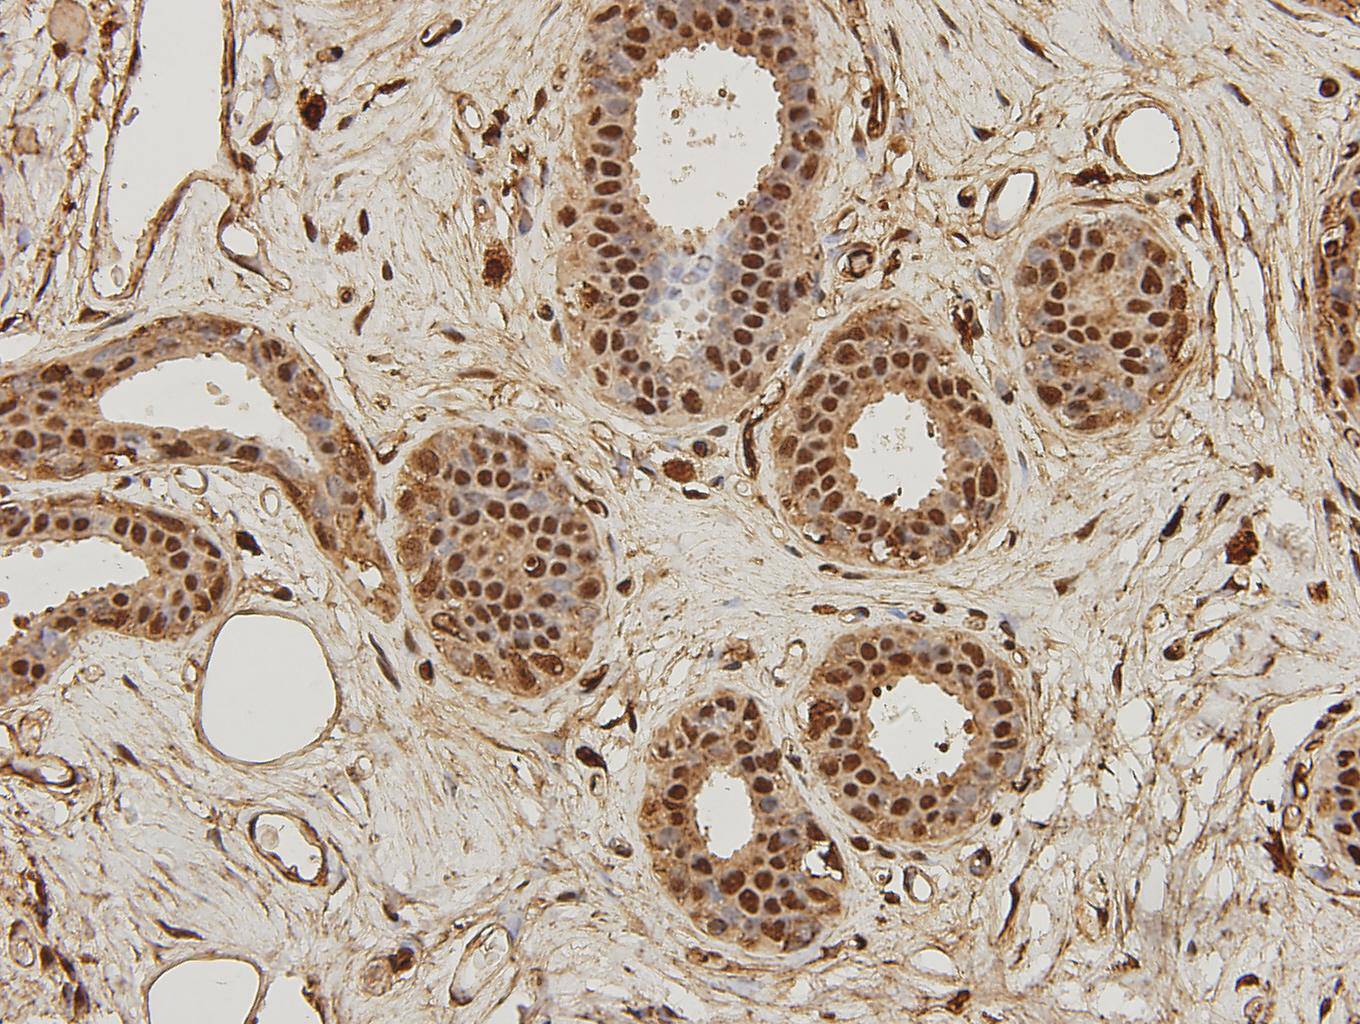

Immunohistochemical analysis of paraffin-embedded human breast carcinoma tissue using anti-NF-κB p105/p50 antibody. Counter stained with hematoxylin.